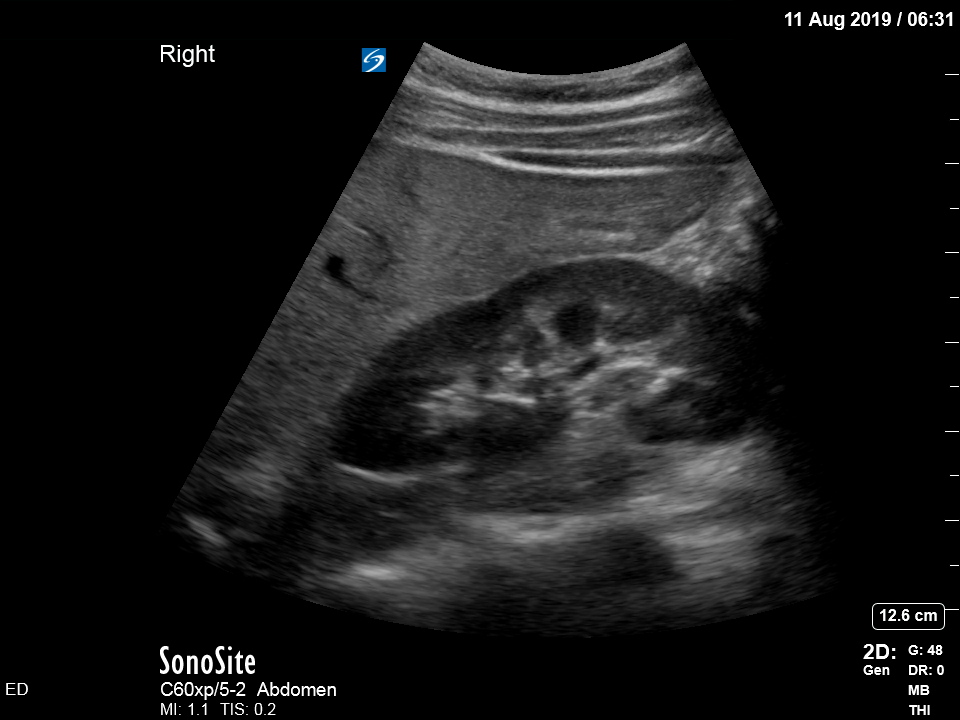

The treating house officer suspected an alternative pathology and bedside ultrasound was performed.

The appearance is typical of acute cholecystitis. The patient was started on IV antibiotics. Images were shown to the surgical registrar who accepted the patient for admission. Formal ultrasound confirmed the findings and the patient went for laparoscopic cholecystectomy within 24hrs. At operation, there was a grossly inflamed gallbladder with an 11mm stone in the neck.

Ultrasound is the formal imaging study of choice for diagnosing gallstones and acute cholecystitis, which makes it a particularly useful POCUS study. The four sonographic signs of acute cholecystitis are:

- Cholelithiasis (stones in the gallbladder, especially if non-mobile)

- Gallbadder wall thickening (there are various published criteria and rules of thumb but generally >4mm is considered abnormal – though it is more about the edematous/irregular appearance than the specific number)

- Pericholecystic fluid

- Sonographic Murphy sign (the patient is tender when the probe presses on the gallbladder)

Notice the typical appearance of the gallstone – the anterior face reflects ultrasound producing a hyperechoic (bright) surface. Because no sounds waves pass through the stone, the area behind it cannot be imaged and instead we see the artefact known as posterior acoustic shadow.